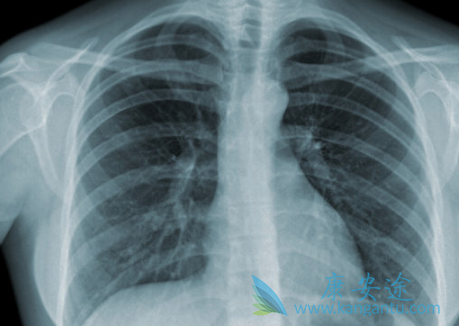

一般来说,肺癌是人们非常害怕的疾病,那么出现这八种情况,非常有可能是肺癌早期症状,千万不能忽视!希望大家以后提高警惕,更关注自己的健康。一、胸闷,绝大部分的胸闷是感冒引起的,但是如果你最近没有感冒,也没有其他的病状的话,那么莫名其妙的胸闷的话,那就应该注意了,因为肺癌的早期的症状也是胸闷。

如果真的出现这种症状的话,也判断不出什么问题,那么建议尽早的去医院检查一下。二、体重莫名下降,体重莫名其妙的下降也是肺癌的前期的症状之一,但是很多时候体重下降的话,都是由于饮食的不规律、生活压力大造成的。三、咽下困难,如果患有肺癌的话,那么肺部就会侵犯或压迫食管可引起咽下困难。四、声音的改变,我们都知道声音除了和喉咙有关,还和肺部的气有关,如果肺出问题了的话,那么就会造成声音的改变。肺癌如果能早期发现早治疗,效果还是比较好的。但遗憾的是,不少肺癌早期症状并不明显,或者虽然出现了一些症状,但患者却并没有重视,错失了早期治疗的机会。五、咳嗽,咳嗽是最常见的症状,如果出现频繁出现咳嗽而且咳嗽现象持续时间很长,尤其是痰带血的情况,那么一定要引起注意。有一半以上的肺癌患者早期会出现连续咳嗽且非常频繁。

另外,肿瘤如果生长在支气管肺组织上,也会可能会引起刺激性咳嗽。所谓“刺激性呛咳”,就好似气道里呛入一粒米饭,身体做出应激反应导致咳嗽不受控制。支气管粘膜上长出小肿瘤,人体也会像气管中呛了一粒米饭一样想把它排出来。六、声音嘶哑,声音嘶哑主要是肿瘤压迫喉返神经造成。控制左侧发音功能的喉返神经由颈部下行至胸部,绕过心脏的大血管返行向上至喉,从而支配发音器官的左侧。因而,若肿瘤侵及纵膈左侧,使喉返神经受到压迫,声嘶便产生了,但却无咽痛及上呼吸道感染的其它症状。七、肿块,在患者刚刚患有肺癌的时候,肿瘤肿块我们是可以摸到的,如果有肿块的发生,患者就需要注意了。癌细胞恶性增殖所形成的,可用手在体表或深部触摸 到。肿瘤转移到淋巴结,可导致淋巴结肿大,某些表浅淋巴结,如颈部淋巴结和腋窝淋巴容易触摸到。八、男性乳房肥大、粗壮指,男性肺癌患者约10%—20%会出现乳腺肥大,多数为双侧肥大,且出现时间比咳嗽、咯血等肺部症状早一年左右。所以,如果你是男性,在排除肥胖的情况下,发现自己乳房突然变大同时手指变粗如鼓槌,就要警惕肺癌鳞状细胞癌。出现这八种情况,有可能是肺癌早期症状,千万不能忽视!